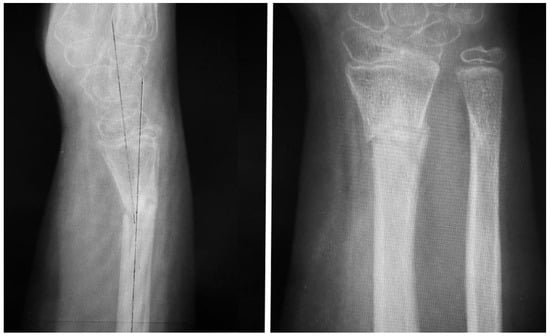

Post-operatively, no immobilization was required and mobility was allowed as tolerated without loading the hand for four weeks. At this time, the passive range of motion was normal while the active range of motion was slightly limited for flexion and extension of the wrist, and the patient underwent a 4-week rehabilitation program involving physical therapy exercises and mobility exercises. At 6 weeks post-operation our patient was pain-free with full range of motion. At week 8 the patient started strengthening exercises, and was allowed to return to high-demand sports after the 4-month follow-up clinical evaluation, which revealed full range of motion, passive and active, and no pain when loading the hand during active flexion and extension. At 12 months, we obtained a radiological control image (Figure 6) that confirmed healing and adequate callus formation as well as bone remodeling.

Figure 6. The 12-month follow-up plain radiographs demonstrating good healing and proper callus formation.